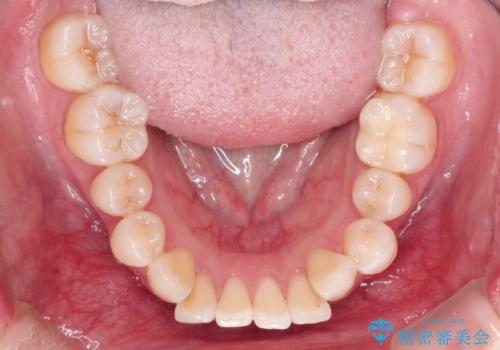

- 出っ歯と全体をきれいにしたいとのことで来院されました。

上顎の歯が全体的に前方に位置しているのと、前から2番目の歯が通常よりも小さい矮小歯という状態でした。

出っ歯をなおすために上顎の前から4番目の歯を抜歯して、引っ込めるのと、前から2番目の歯に通常の大きさのオールセラミックを装着して整った歯並びにすることにしました。